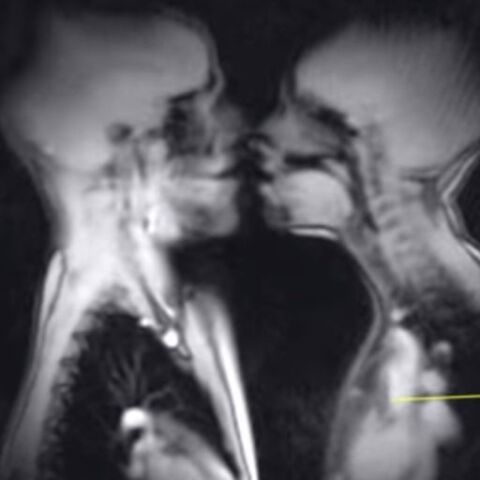

Έτσι είναι το σεξ μέσα από το βλέμμα ενός μαγνητικού τομογράφου

Μοναδικό βίντεο καταγράφει τις πιο μύχιες στιγμές μας